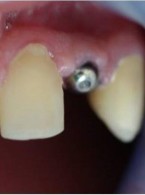

Uzupełnienie wrodzonego braku zawiązków stałych zębów siecznych bocznych w szczęce...

Maciej Miczek